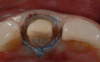

Fig 6. Tooth preparation has been completed.

Figure 6

Figure 6 through Figure 9 demonstrate the use of retraction paste and a cap. An upper bicuspid was prepared (Figure 6), and some bleeding occurred due to the clinician working below the existing restorations. Retraction paste was then applied (Figure 7), but there was still some residual bleeding. The clinician then had the patient close on the retraction cap to stop the bleeding (Figure 8). Some blanching occurred as the patient bit into the cap. The patient will hold that position depending on how much bleeding occurs. Figure 9 shows the exposed margin ready for impressioning. In this case, the retraction cap was kept in place with the patient biting down on it for 2 to 3 minutes instead of 1 to 2 minutes because there was a fair amount of bleeding initially.